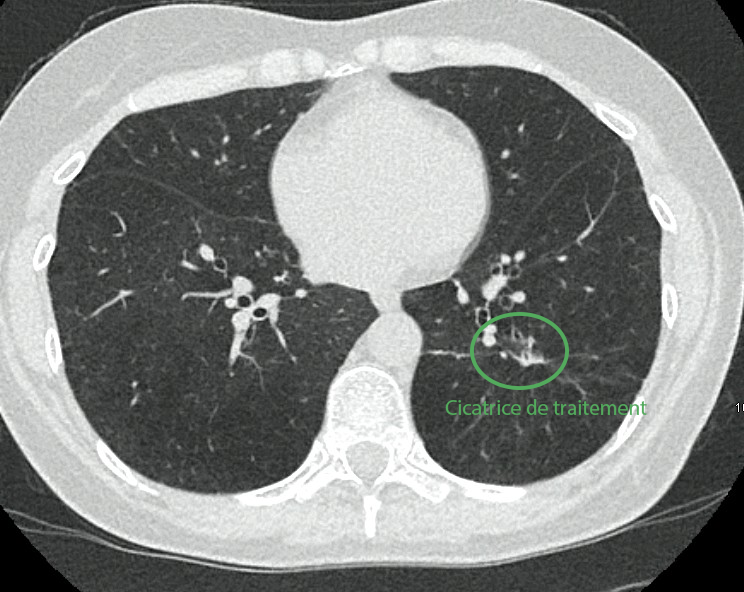

Traitement pulmonaire par cryoablation

La lésion pulmonaire est traitée par cryothérapie, permettant une destruction efficace tout en évitant une chirurgie lourde (lobectomie).

Un pneumothorax, complication attendue, est pris en charge simplement avec un drain temporaire.

En images

Images du traitement des organes (poumon et foie) avant, pendant et après le traitement.